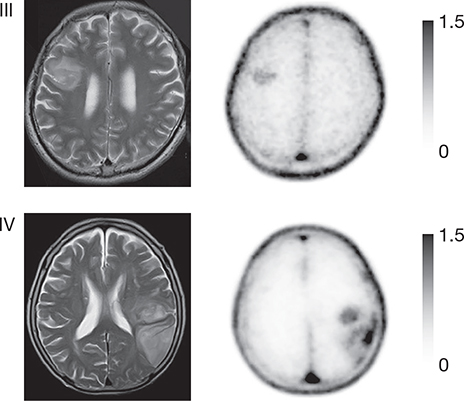

All four nucleoside-based agents – 18F-FLT, 11C-4DST, 18F-FMAU and 11C-TdR – are based on thymidine, which pairs with adenine in the DNA double helix and is therefore directly involved in cellular proliferation. These agents use equilibrative nucleoside transporter 1 (ENT1) to enter cells (Figure 5). Although ENT1 is present throughout the brain including endothelial cells (Table 3), none of these agents can readily cross the BBB leading to a high T/N ratio. In clinical practice, uptake of either agent will therefore reflect at least increased BBB permeability next to ENT1 overexpression (105). After entering the cell, most become phosphorylated by thymidine kinase 1 (TK1), which is cell-cycle dependent and therefore upregulated in tumor cells, or TK2, which is restricted to mitochondria and is cell-cycle independent. Only 18F-FLT and 11C-4DST interact with TK1: 18F-FLT subsequently becomes trapped in the cytoplasm because it lacks an essential hydroxyl group, causing uptake to indirectly reflect increased cellular proliferation, while 11C-4DST becomes incorporated into DNA, thereby directly reflecting increased DNA synthesis and proliferation (Figure 5) (105). Kinetic analyses will be necessary to distinguish uptake due to disrupted BBB from that due to increased cellular proliferation(106), decreasing their sensitivity for brain tumor cells compared to amino acid agents like 11C-MET and 18F-FET (Figure 6), and they should not be used for e.g., recurrent non-enhancing brain tumors (107, 108). However, uptake of 18F-FLT has been shown to differentiate between grade III and IV gliomas, and is sometimes seen in non-enhancing areas on MRI, suggesting not all uptake is BBB-related; it has also been suggested that even a small number of glioma cells can cause BBB disruption without additional contrast agent leakage (108, 109). Tumor uptake of 18F-FLT can also be used to predict tumor progression in meningiomas (110). Background uptake of 11C-4DST is paradoxically high compared with 18F-FLT, and it has not been studied much (111). 18F-FMAU becomes phosphorylated by TK2, raising the question whether uptake really reflects cellular progression, while 11C-TdR is not used anymore because of its high catabolism into 11C-CO2 which causes significant background uptake.

Figure 6. T1-weighted post-contrast (cT1), T2-weighted (T2), 18F-FLT PET ([18]F-FLT) and 18F-FET ([18]F-FET) images of a patient with a non-enhancing glioblastoma, WHO grade IV. The lesion is hyperintense on the T2-weighted image but does not show contrast enhancement. Increased uptake in the T2-hyperintense region can clearly be seen on the 18F-FET PET image, but there is no uptake visible on the 18F-FLT PET image, illustrating the drawback of PET agents that cannot easily cross the BBB. This figure is reproduced – with new figure legend appropriate for current article – from Nowosielski et al. (2014), Figure 1, under the terms of the Creative Commons Attribution 4.0 International (CC BY) License (http://creativecommons.org/licenses/by/4.0) (107).